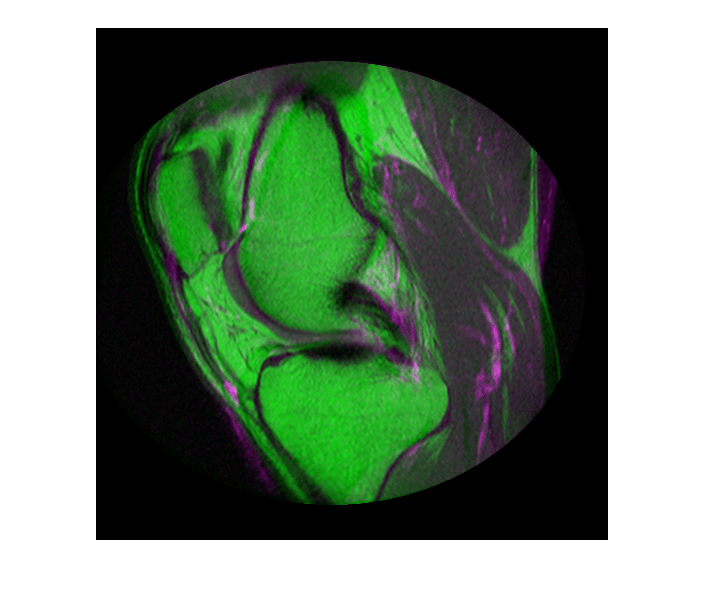

Считайте два изображения. Этот пример использует два магнитно-резонансных (МРТ) изображения колена. Фиксированное изображение является спин-эхо-изображением, в то время как движущееся изображение является спин-эхо-изображением с восстановлением инверсии. Два сагиттальных среза были получены одновременно, но немного не совпадают.

imshowpair(fixed, moving,'Scaling','joint')

Figure contains an axes. The axes contains an object of type image.

Просмотр зарегистрированных изображений.

imshowpair(fixed, movingRegistered,'Scaling','joint')